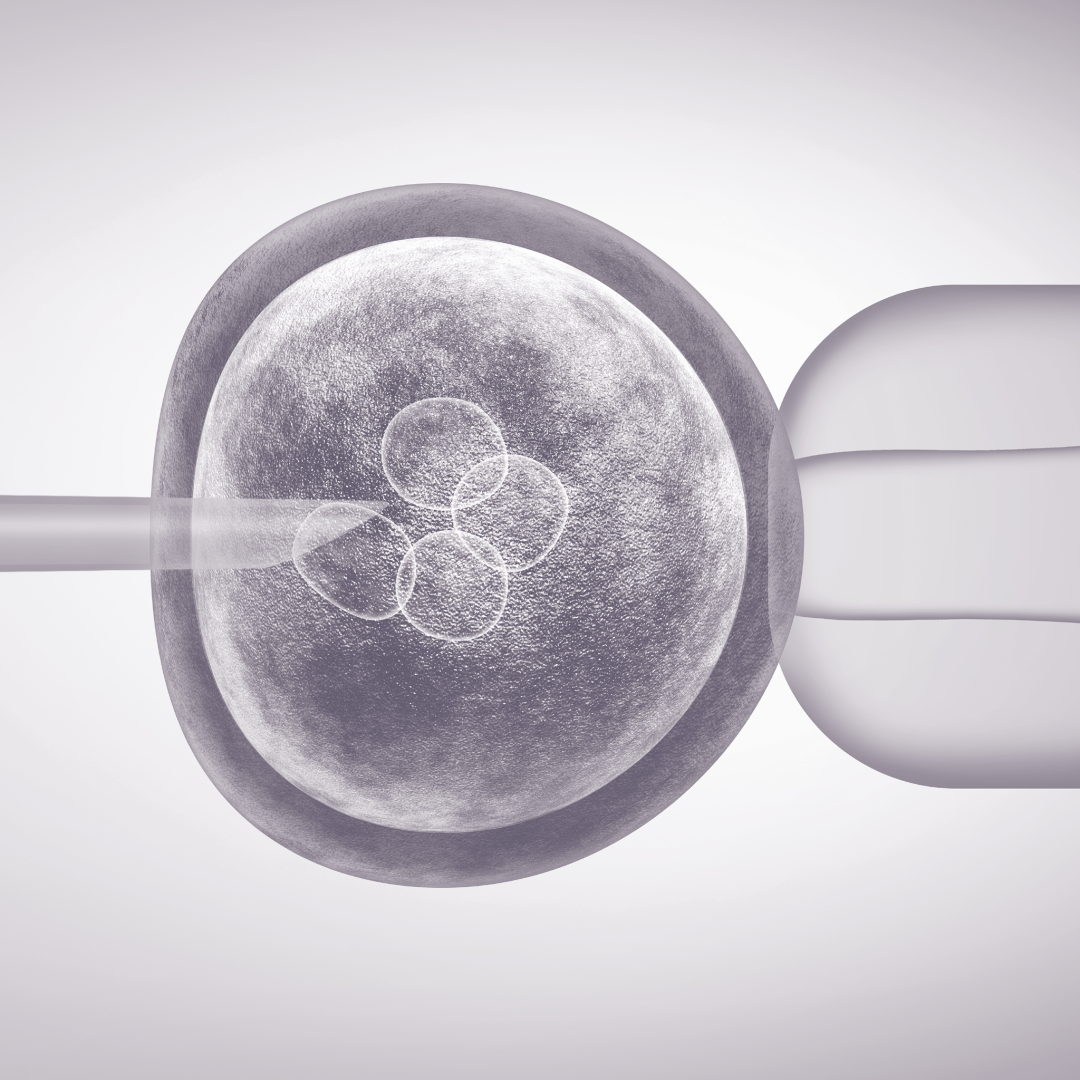

MGV en leefstijl

Medisch Geassisteerde Voortplanting (MGV), zoals in-vitrofertilisatie, intracytoplasmatische sperma-injectie of donorinseminatie, kan oplossingen bieden bij vruchtbaarheidsproblemen. Het zijn echter tevens ingrijpende en kostbare procedures. Het aanpakken van leefstijlfactoren kan verstoorde fysieke werkingsmechanismen corrigeren, de eicelrijping en -kwaliteit herstellen en daarmee het gebruik van deze procedures overbodig maken.1 Een te hoge of lage calorie-inname en de afwezigheid van voedingsstoffen spelen bijvoorbeeld een rol bij onvruchtbaarheid veroorzaakt door endometriose en ovulatiestoornissen. Intensieve sportbeoefening kan de hypothalamus-hypofyse-as beïnvloeden, waardoor de menstruatie uitblijft. Matige fysieke activiteit daarentegen verbetert de ovariële functie en vruchtbaarheid, vooral bij vrouwen met obesitas of met stress. Ook is er steeds meer onderzoek naar het verband tussen een gezond darm- en vaginaal microbioom en vrouwelijke vruchtbaarheid.2 Er bestaan dus voldoende aanknopingspunten voor zinvolle leefstijlinterventies.